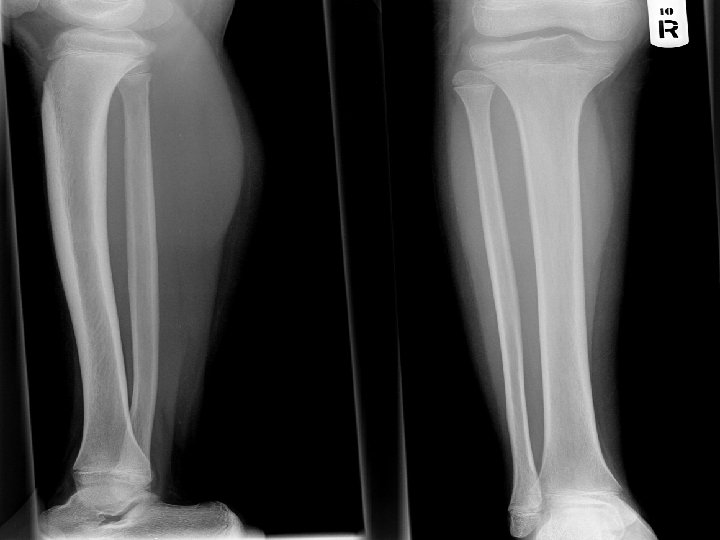

X-Ray

Progression v 20/08/52 OPD Follow up, ปวดขามากโดยเฉพาะทบรเวณนอง admit for further investigation § § § , ซดลง Investigation : plain X-ray leg [right], นด U/S right leg Consult pain: MO IV prn for pain Blood component as needed Continue Bonefos Continue Radiation